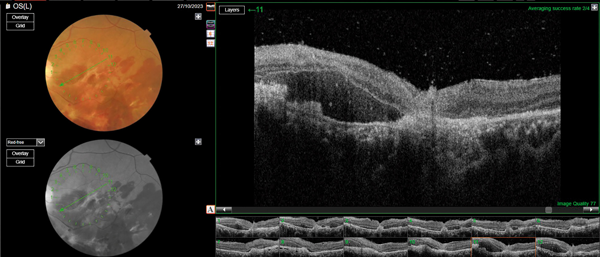

Ante estos hallazgos se solicitó una serie de estudios complementarios. Se realizó una tomografía en la que se encontraron múltiples trazos de fractura en las paredes del seno maxilar y piso de la órbita izquierda, etmoides y pared póstero-interna sin evidencia de cuerpo extraño intraorbitario. En la tomografía de coherencia óptica macular se observó el perfil retinal anterior alterado, irregular y asimétrico; contorno foveolar ausente; ausencia de paralelismo en las capas retinales con interrupción de la capa elipsoides; sectores con hemorragias a nivel subretinal e imágenes hiperreflectivas en sector foveolar sin sombra acústica posterior (fig. 2).

Figura 2. OCT de ojo izquierdo: perfil retinal anterior alterado, irregular y asimétrico; contorno foveolar ausente; ausencia de paralelismo en las capas retinales con interrupción de la capa elipsoides.